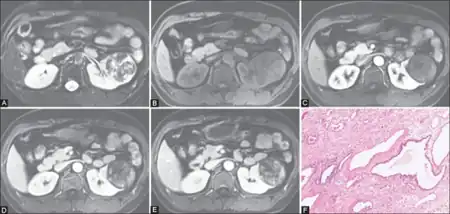

| Congenital mesoblastic nephroma, classic type, with typical features.[1] H&E stain. | |

- 1) The classic type occurs in ~39% of patients. Its tissues show interlaced spindle-shaped smooth muscle cells evidencing low mitotic activity with no evidence of tumor encapsulation; and infiltration into and entrapment of normal kidney tissue.[2]

- 2) The cellular type occurs in ~42% of patients.[2] Its tissues show densely packed fibrosarcoma-like cells evidencing high rates of mitosis, less infiltration of normal kidney tissue, and multiple areas of hemorrhage and cysts.[2][4]

- 3) The mixed type occurs in ~19% of patients. It shows a mixture of the classic and cellular types in different areas of the neoplasm.[2]

- ↑ Image by Mikael Häggström, MD. Source for typical features: Ellen D’Hooghe, M.D., Gordan M. Vujanic, M.D., Ph.D. "Congenital mesoblastic nephroma". Pathology Outlines. Archived from the original on 2022-01-19. Retrieved 2022-10-11.